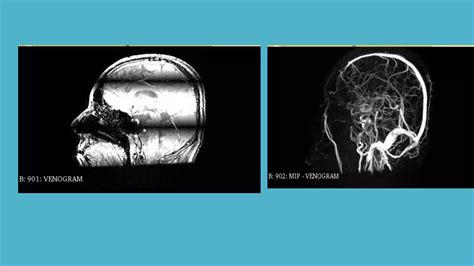

Magnetic Resonance Venography (MRV) is a sophisticated medical imaging technique that uses magnetic fields and radio waves to generate detailed images of the cerebral veins. Unlike a standard MRI, which primarily looks at the brain tissue itself, an MRV is specifically designed to assess blood flow and identify potential abnormalities within the venous system.

Doctors frequently use this scan to detect issues such as cerebral venous thrombosis (blood clots in the brain's veins), narrowing of the veins (stenosis), or other vascular anomalies that might be affecting cerebral circulation.

After the scan is complete, a neuroradiologist—a doctor who specializes in brain imaging—will analyze the images. They will look for signs of blood clots, narrowed vessels (stenosis), or malformations that could be disrupting normal circulation. Your primary physician will receive a formal report and will schedule a follow-up appointment to discuss these findings with you in detail and determine the appropriate path forward for treatment if necessary.